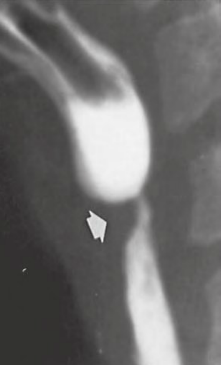

“Bull’s Eye” / Target lesion DDx